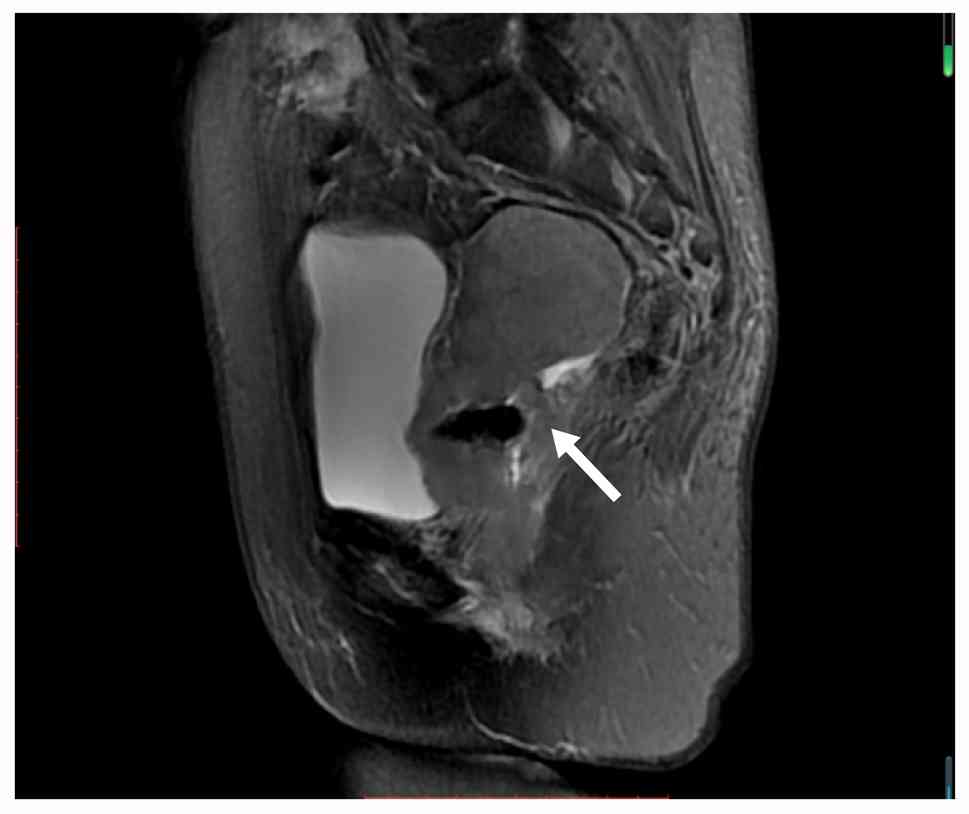

Examples of MRI diagnostic images from multiple patients are shown in Fig. 1, Fig. 2, Fig. 3, Fig. 4, Fig. 5. Fig. 1 shows an irregular soft-tissue mass in the cervical region, clearly visible on the axial sequence of T2-weighted fat-saturated imaging. The mass may suggest cervical lesions or tumors. Fig. 2 displays multiple lymph node metastases in the pelvic region on the axial sequence of DWI. The high-signal areas indicate that the lymph nodes might be affected by tumor metastasis. Fig. 3 reveals an irregular soft-tissue mass in the cervical region on the sagittal sequence of T2-weighted fat-saturated imaging. The mass is shown to have extended into the vaginal area, with the sagittal view aiding in the assessment of the lesion's longitudinal extent. Fig. 4 displays an irregular soft-tissue mass in the cervical region on T1-weighted enhanced imaging. The mass shows significant heterogeneous enhancement, suggesting that the lesion may be malignant. Fig. 5 illustrates a lesion in the cervical and vaginal regions on the sagittal sequence of T1-weighted enhanced imaging. The lesion area demonstrates heterogeneous enhancement, further indicating the possibility of a malignant tumor.

T2-weighted fat-saturated axial

sequence showing an irregular soft-tissue mass (white arrow) in the

cervical region.

Figure 1.

T2-weighted fat-saturated axial sequence showing an irregular soft-tissue mass (white arrow) in the cervical region.